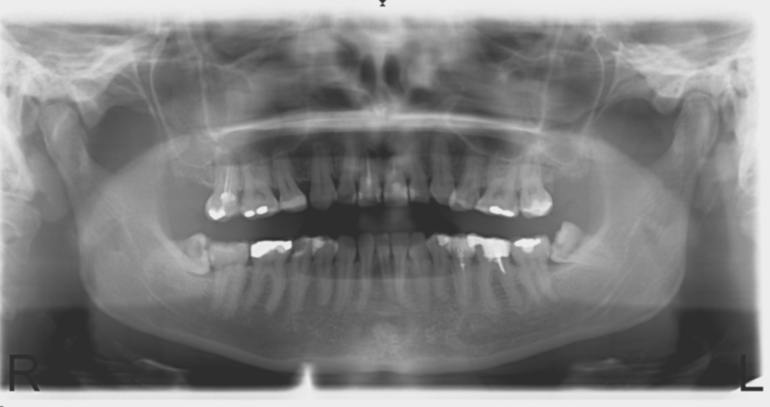

Нижние зубы мудрости растут перпендикулярно. Сделала ортопантомограмму, врач сказал случай сложный и не стоит их дергать пока не начнут болеть. Знакомая стоматолог (не практикующая уже), сказала, что такое только в стационаре удалять надо.

Вот снимок.

Здравствуйте!Удалить эти зубы ,действительно, нужно. Но, перед удалением, нужно сделать компьютерную томограмму (КТ). И с ней приехать на консультацию.Показаний к стационару нет. Просто удалять нужно будет по одному зубу.89255066177 Телефон клиники. Просите записать к Лушанину Михаилу Сергеевичу (хирург-имплантолог). Перед визитом сделайте КТ.